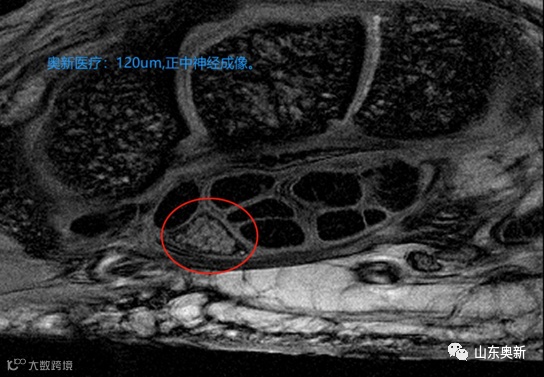

奥新医疗3.0T四肢关节磁共振优势:

奥新医疗3.0T四肢关节磁共振是人体四肢关节成像诊断中的劳斯莱斯,具有高清影像、扫描更快、无幽闭感、静音、排位舒适等优势,产品填补国内外空白,技术水平达到国际领先。